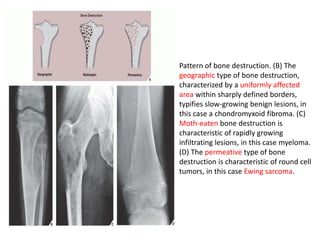

Pattern of bone destruction. (B) The

geographic type of bone destruction,

characterized by a uniformly affected

area within sharply defined borders,

typifies slow-growing benign lesions, in

this case a chondromyxoid fibroma. (C)

Moth-eaten bone destruction is

characteristic of rapidly growing

infiltrating lesions, in this case myeloma.

(D) The permeative type of bone

destruction is characteristic of round cell

tumors, in this case Ewing sarcoma.